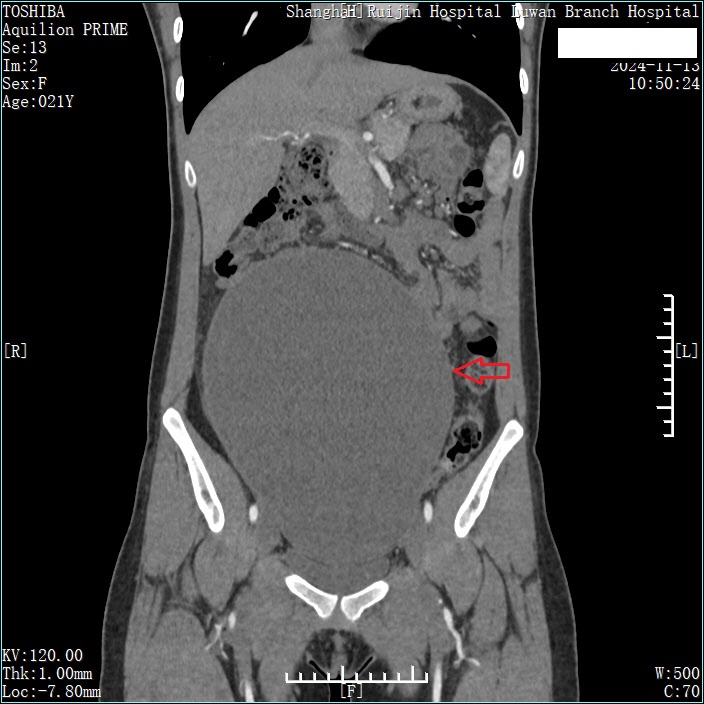

为尽可能在最大限度保留生育功能的基础上切除肿瘤,王明亮教授团队联合妇科朱岚教授团队一起对小宁的病情做了评估,制定了详细的手术方案。术前CT评估显示中下腹部见巨大囊性肿块,大小为18.7*10.8*23.4cm。

在入院的第三天小宁接受了手术治疗,王明亮教授团队联合妇科朱岚主任团队精心设计了下腹部不到10cm的远小于肿块大小的切口,先对肿块进行抽液减压,抽出囊液约2400ml后再进行探查,肿块来源于右侧卵巢。完整剥离肿瘤并且保留了右侧卵巢,最大限度地保留生育功能。